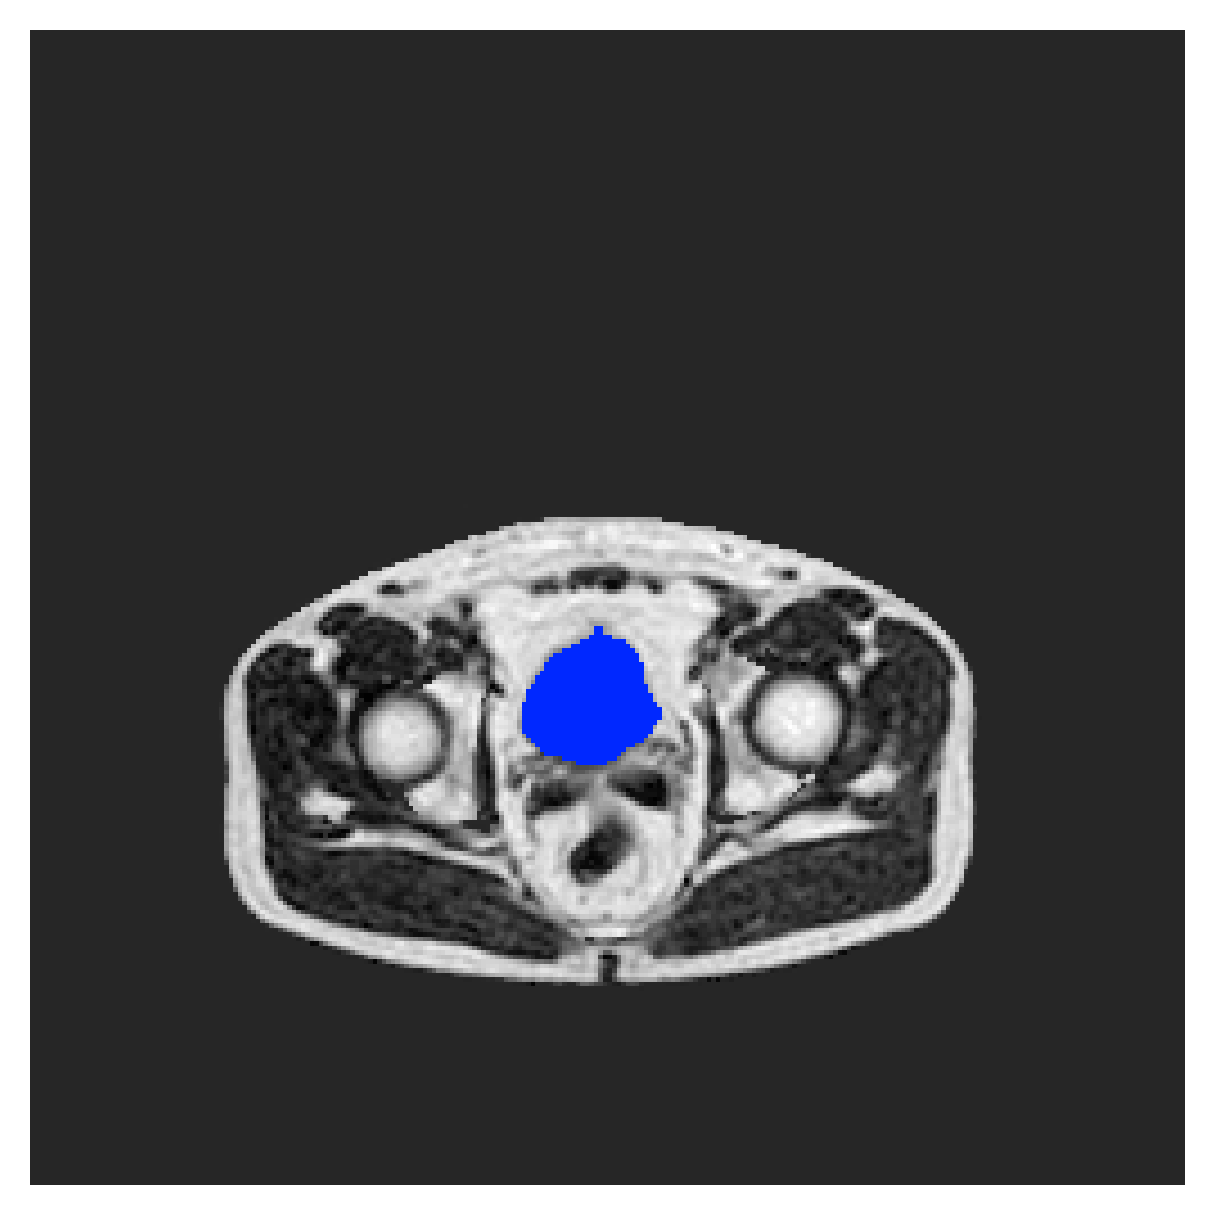

POEM

The Prospective investigation of Obesity, ENergy production and Metabolism (POEM) is a local (not currently publicly available; PI: L. Lind, see [22] for details) cohort of whole-body fat/water separated MR images. Full annotations of the liver, kidneys, bladder, pancreas and spleen are available for 50 subjects, providing a challenging segmentation dataset with heavily imbalanced classes of varying shapes. The resolution of the data is anisotropic, with reconstructed voxel size of in left-right, anterior-posterior and foot-head directions, respectively. For additional technical details regarding the acquisition and specifications of the images see [22].

The images contain two channels, one for water and one for fat content. For training, we normalize the volumes (per channel) and use 2D slices in the coronal plane, sized . The weak annotations are created synthetically, following the same procedure as described for the ACDC dataset.

5.2 Abdominal organ segmentation

Using 2D distance maps

In Table 3, the average DSC and HD95 results are shown (both using 2D and 3D distance maps) for the task of abdominal organ segmentation in POEM data (for boxplots see figures 8 and 9). We see that training with and (with distances calculated on 2D slices) performs comparably, while using and produces lower scores in both DSC and HD95 metric. On this dataset, the CRF-loss is able to compete with the boundary loss-based training strategies, even outperforming them on most classes. Most notably, all models trained with boundary loss appear to have a hard time segmenting the liver. We hypothesize this may be due to extremely severe class imbalance, as the liver covers a very large area compared to the rest of the classes. It is thus also more strongly affected by undersegmentations.